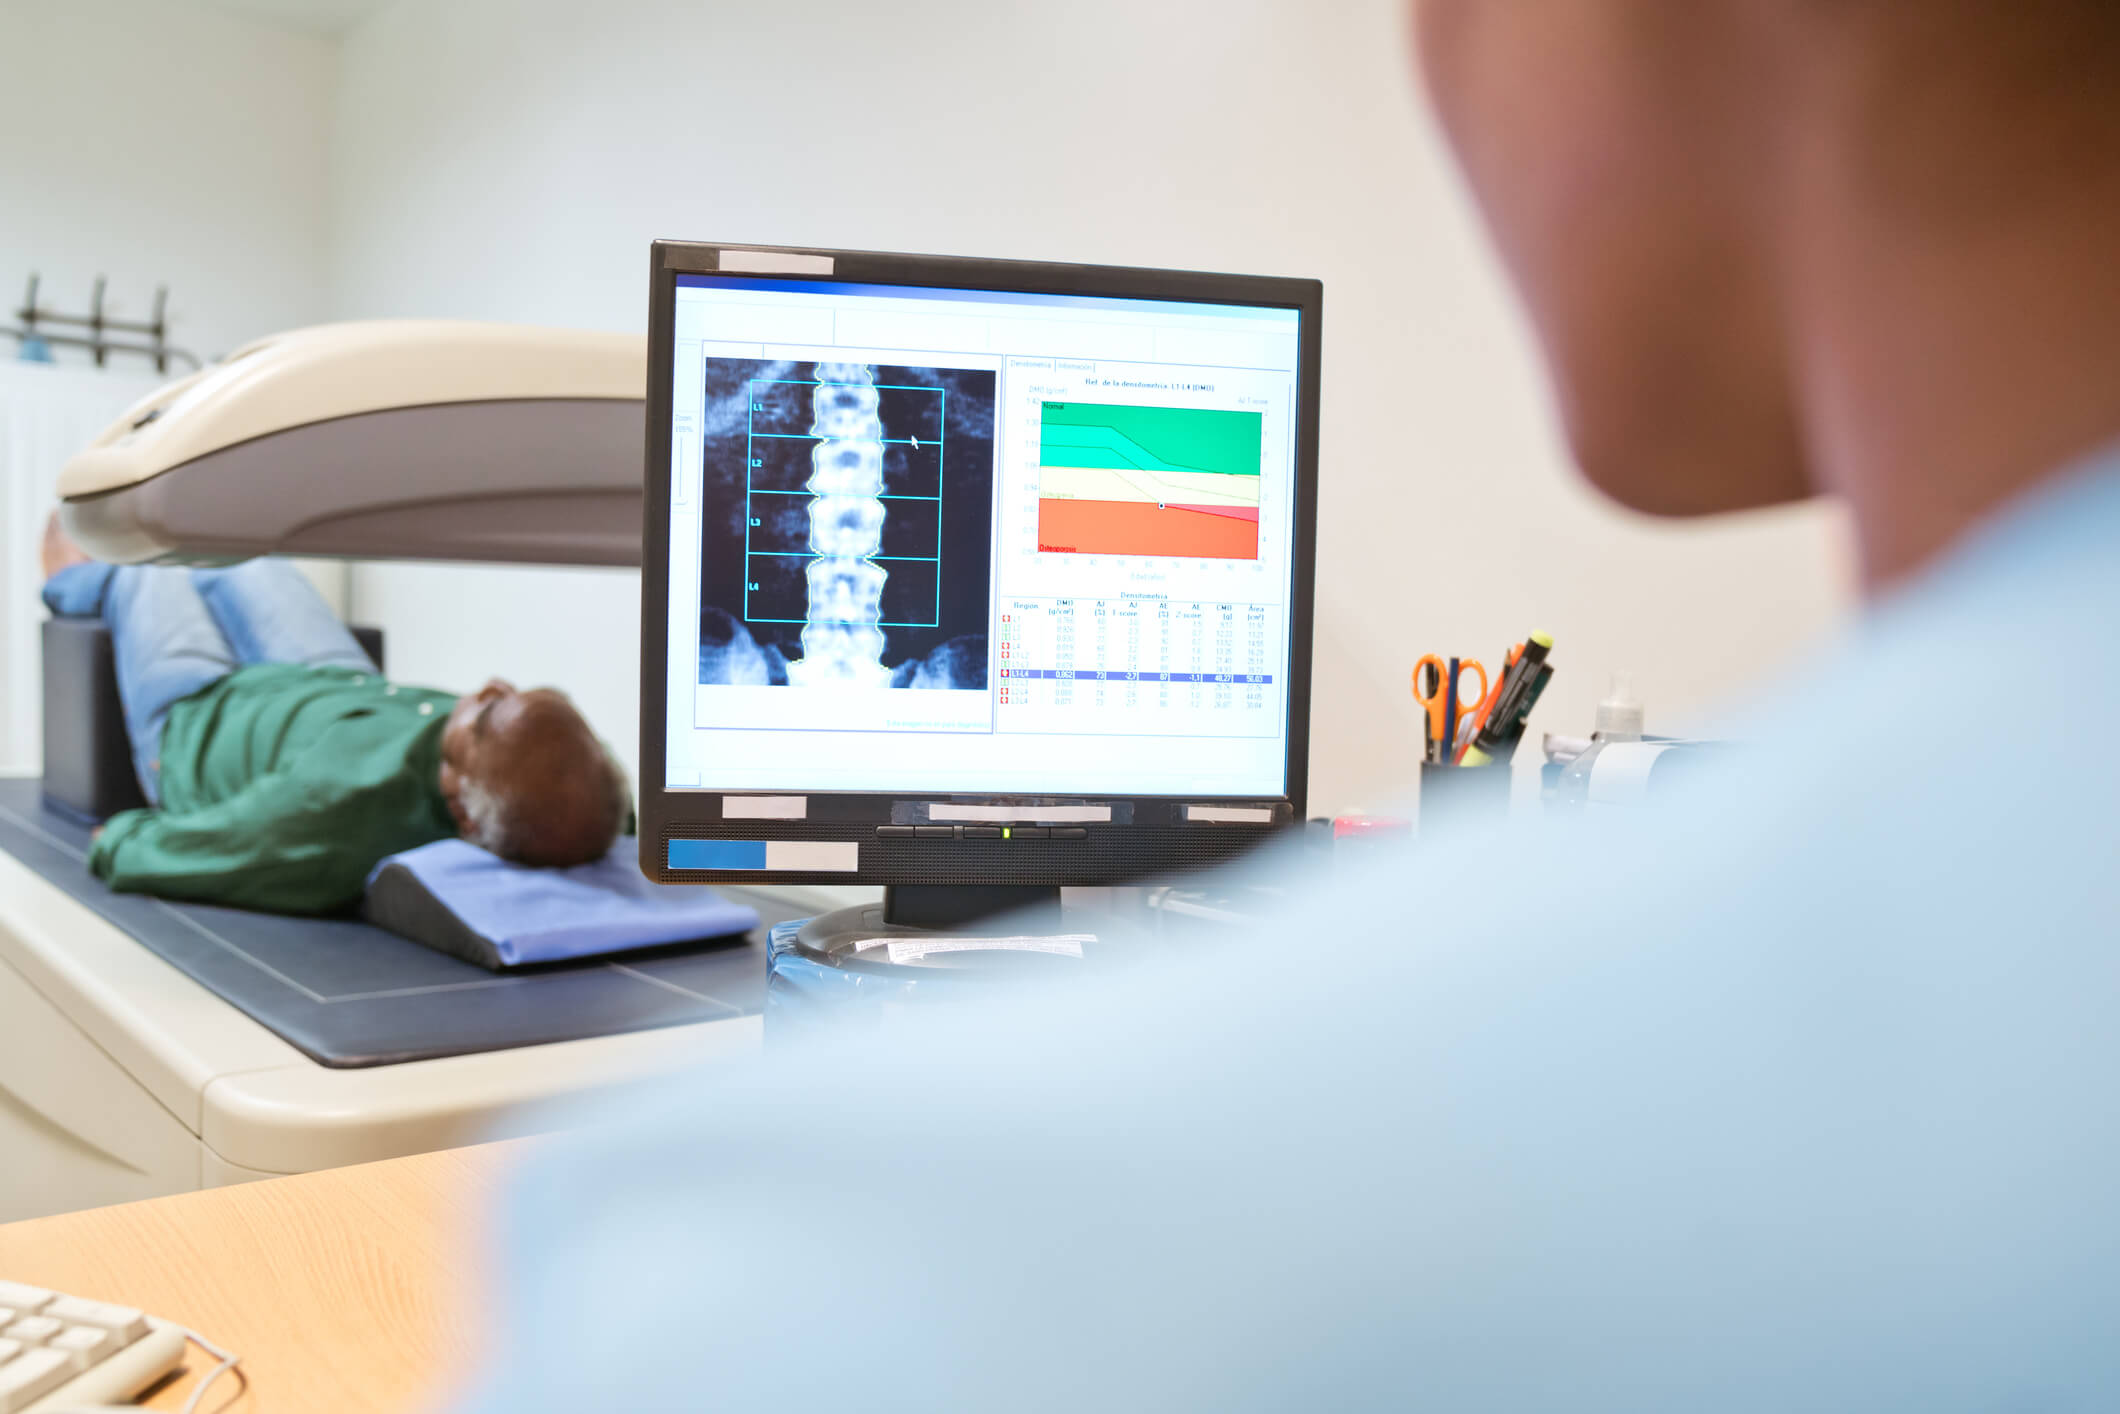

Tecnologia de ponta

Investimos continuamente nas mais modernas tecnologias, pensando em melhor atendê-lo.

Exames precisos

Efetuamos os mais importantes e modernos exames e diagnósticos por imagem.

A Singular Saúde atua no mercado oferecendo experiência em diagnóstico por imagem, investindo continuamente nas mais modernas tecnológicas, pensando no seu futuro. Com uma equipe multidisciplinar, oferece um novo conceito de espaço, qualidade em serviços e resultados mais precisos.